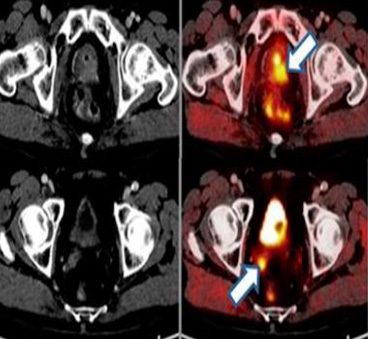

PET/COLINA en el cáncer de próstata

A la hora de valorar el papel de la tomografía por emisión de positrones (PET) en el cáncer de próstata, es importante analizar los diferentes radiotrazadores emisores de positrones disponibles.